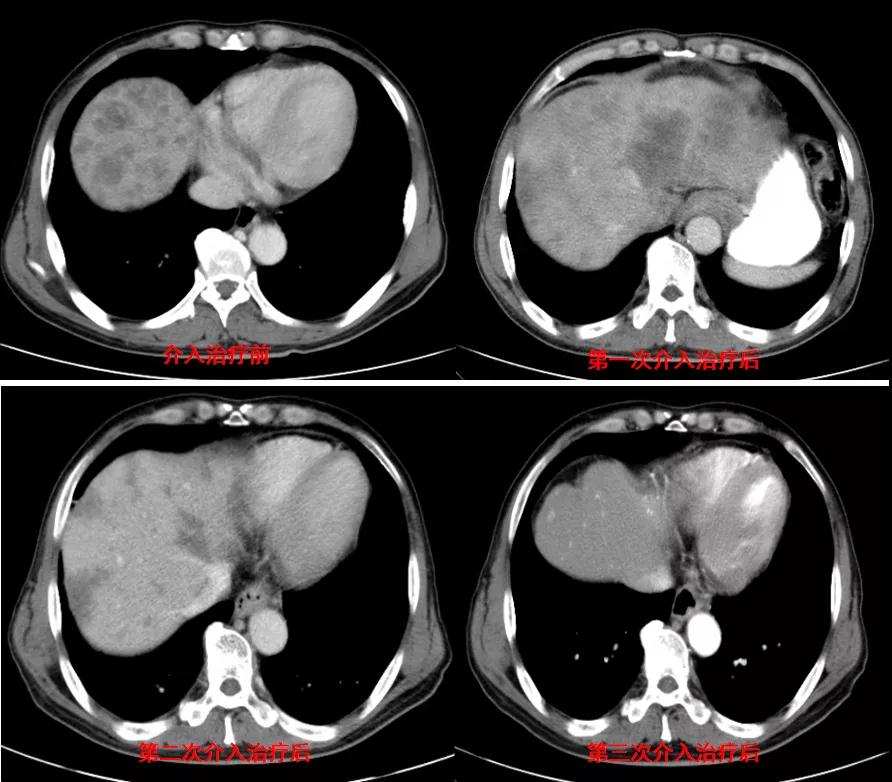

腹部CT检查(2020年11月10日):贲门胃底占位,肝内多发转移灶,腹主动脉旁多发淋巴结肿大,见图1。

图1